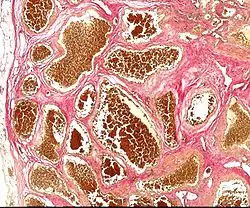

Naczyniaki jamiste ośrodkowego układu nerwowego (ang. cavernous angioma) – łagodne guzy naczyniowe, należące do guzów hamartomatycznych. Mogą być dziedziczone autosomalnie dominująco. Mają najczęściej przebieg bezobjawowy, rzadko są przyczyną napadów padaczkowych i ubytków neurologicznych. W połowie przypadków wada ta rozpoznawana jest przypadkowo. Leczeniem z wyboru jest leczenie chirurgiczne.